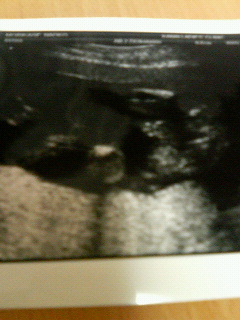

身長が20センチぐらいで、スラッとしているみたいなんだけど、体重が220グラム。

先生が言うわりには、まぁまぁの小さめちゃん。

さてさて逆子ちゃんなので、最初は分かりづらかったんだけど、よ~く見ると何やらお股の間にご立派なポチッとしたものが…

分かりづらいけど、右側で股を広げてます。ポチッとしたもの分かるかしら?